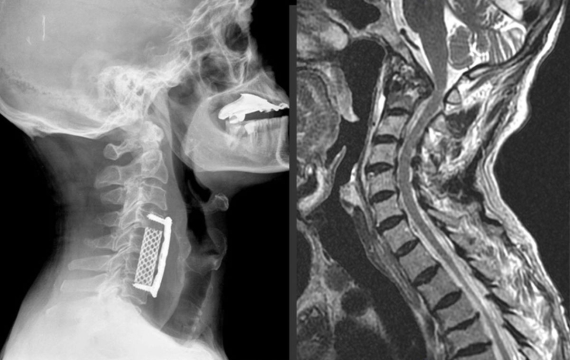

Casos clínicos y resultados obtenidos en cirugía cervical

En la cirugía cervical, cada caso clínico requiere un abordaje distinto. Sin embargo, en términos generales, la cirugía cervical se ha utilizado con éxito para tratar patologías tales como hernias, discos intervertebrales y osteofitos que afectan la columna cervical. Aquí mostramos algunos casos clínicos y los resultados obtenidos:

• Caso 1: Paciente de 45 años presentaba hernia discal cervical en el disco C5-C6. Tras la realización de una discectomía cervical anterior y fusión, el paciente mejoró su sintomatología. Posteriormente, se realizaron pruebas de imagen y radiografías para evaluar la fusión vertebral, que resultaron satisfactorias.

• Caso 2: Paciente de 50 años presentaba dolor cervical crónico y debilidad en el brazo izquierdo debido a la presencia de una hernia discal cervical en el nivel C6-C7. Tras la realización de una corpectomía y fusión posterior con sistema de fijación, el paciente mejoró significativamente su calidad de vida con reducción en los síntomas antes descritos.

• Caso 3: Paciente de 60 años que presentaba dolor y rigidez cervical de larga duración debido a la presencia de osteofitos que comprimían raíces nerviosas. Se realizó una cirugía de implantación de disco cervical artificial en el nivel C5-C6, obteniéndose una mejora significativa en la movilidad de la columna cervical y reducción de la sintomatología previa.

Image

En todos estos casos, se siguieron las recomendaciones postoperatorias y se realizaron pruebas de imagen para evaluar la evolución clínica del paciente. En general, los pacientes presentaron mejorías significativas en la calidad de vida y reducción de síntomas como el dolor, debilidad o limitaciones en la movilidad. Sin embargo, es importante tener en cuenta que la cirugía cervical, al igual que cualquier intervención quirúrgica, tiene sus propios riesgos y complicaciones, y debe ser realizada por profesionales altamente capacitados y especializados en la materia.